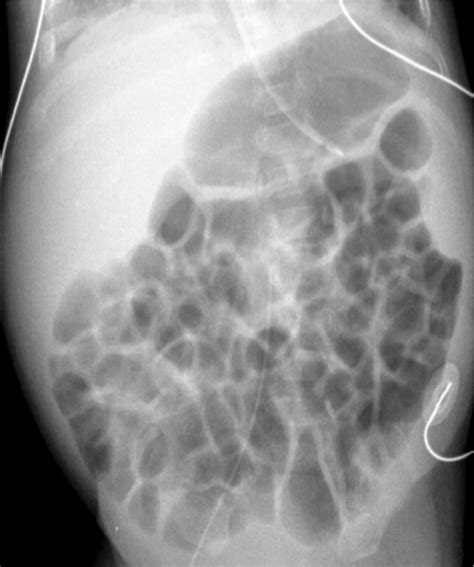

The human gastrointestinal tract naturally contains a certain amount of gas. This gas is a byproduct of digestion, the breakdown of food by bacteria in the colon, and the air we swallow while eating or drinking. A nonobstructive bowel gas pattern refers to the typical, expected distribution of gas throughout the intestines as seen on imaging, which does not indicate a clinical obstruction.

In a healthy individual, gas moves through the bowels alongside digested food and stool, eventually being passed as flatus or absorbed. When a radiologist describes the pattern as "nonobstructive," they are confirming that the gas is scattered in a way that is consistent with normal physiological function, rather than being trapped in a dilated loop that indicates a mechanical blockage.

Gas Distribution Scattered throughout the small and large bowel. Localized to specific, dilated segments.

Bowel Diameter Within normal physiological limits. Significantly dilated (swollen).

Gas-Fluid Levels Minimal or absent. Prominent, indicating trapped air and liquid.